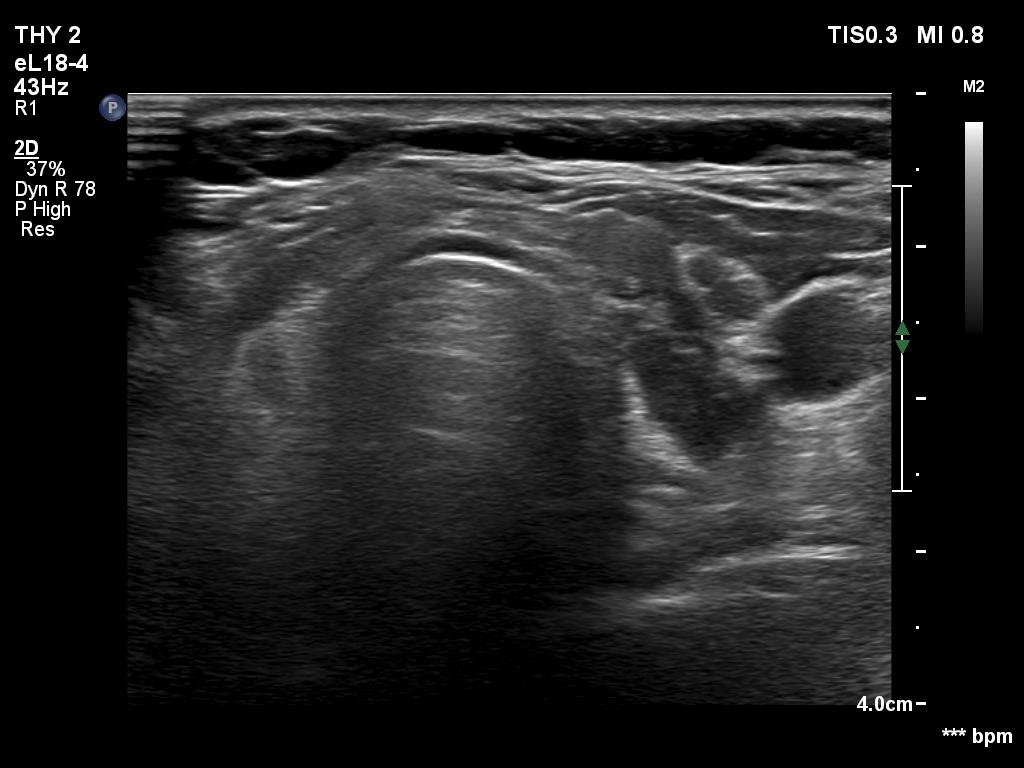

Ultrasonography. The thyroid was mainly composed of hypoechoic islets which floated in less hypoechoic background. These lesions had irregular, lobulated margins and showed no vascularity.

Comment. The presentation was not entirely characteristic of Hashimoto's thyroiditis. Nevertheless, the multiplicity of the lesions, the irregular borders and the moderately hypoechoic non-lesional part of the lobe all argued for being these lesions not true nodules but more active foci of thyroiditis.